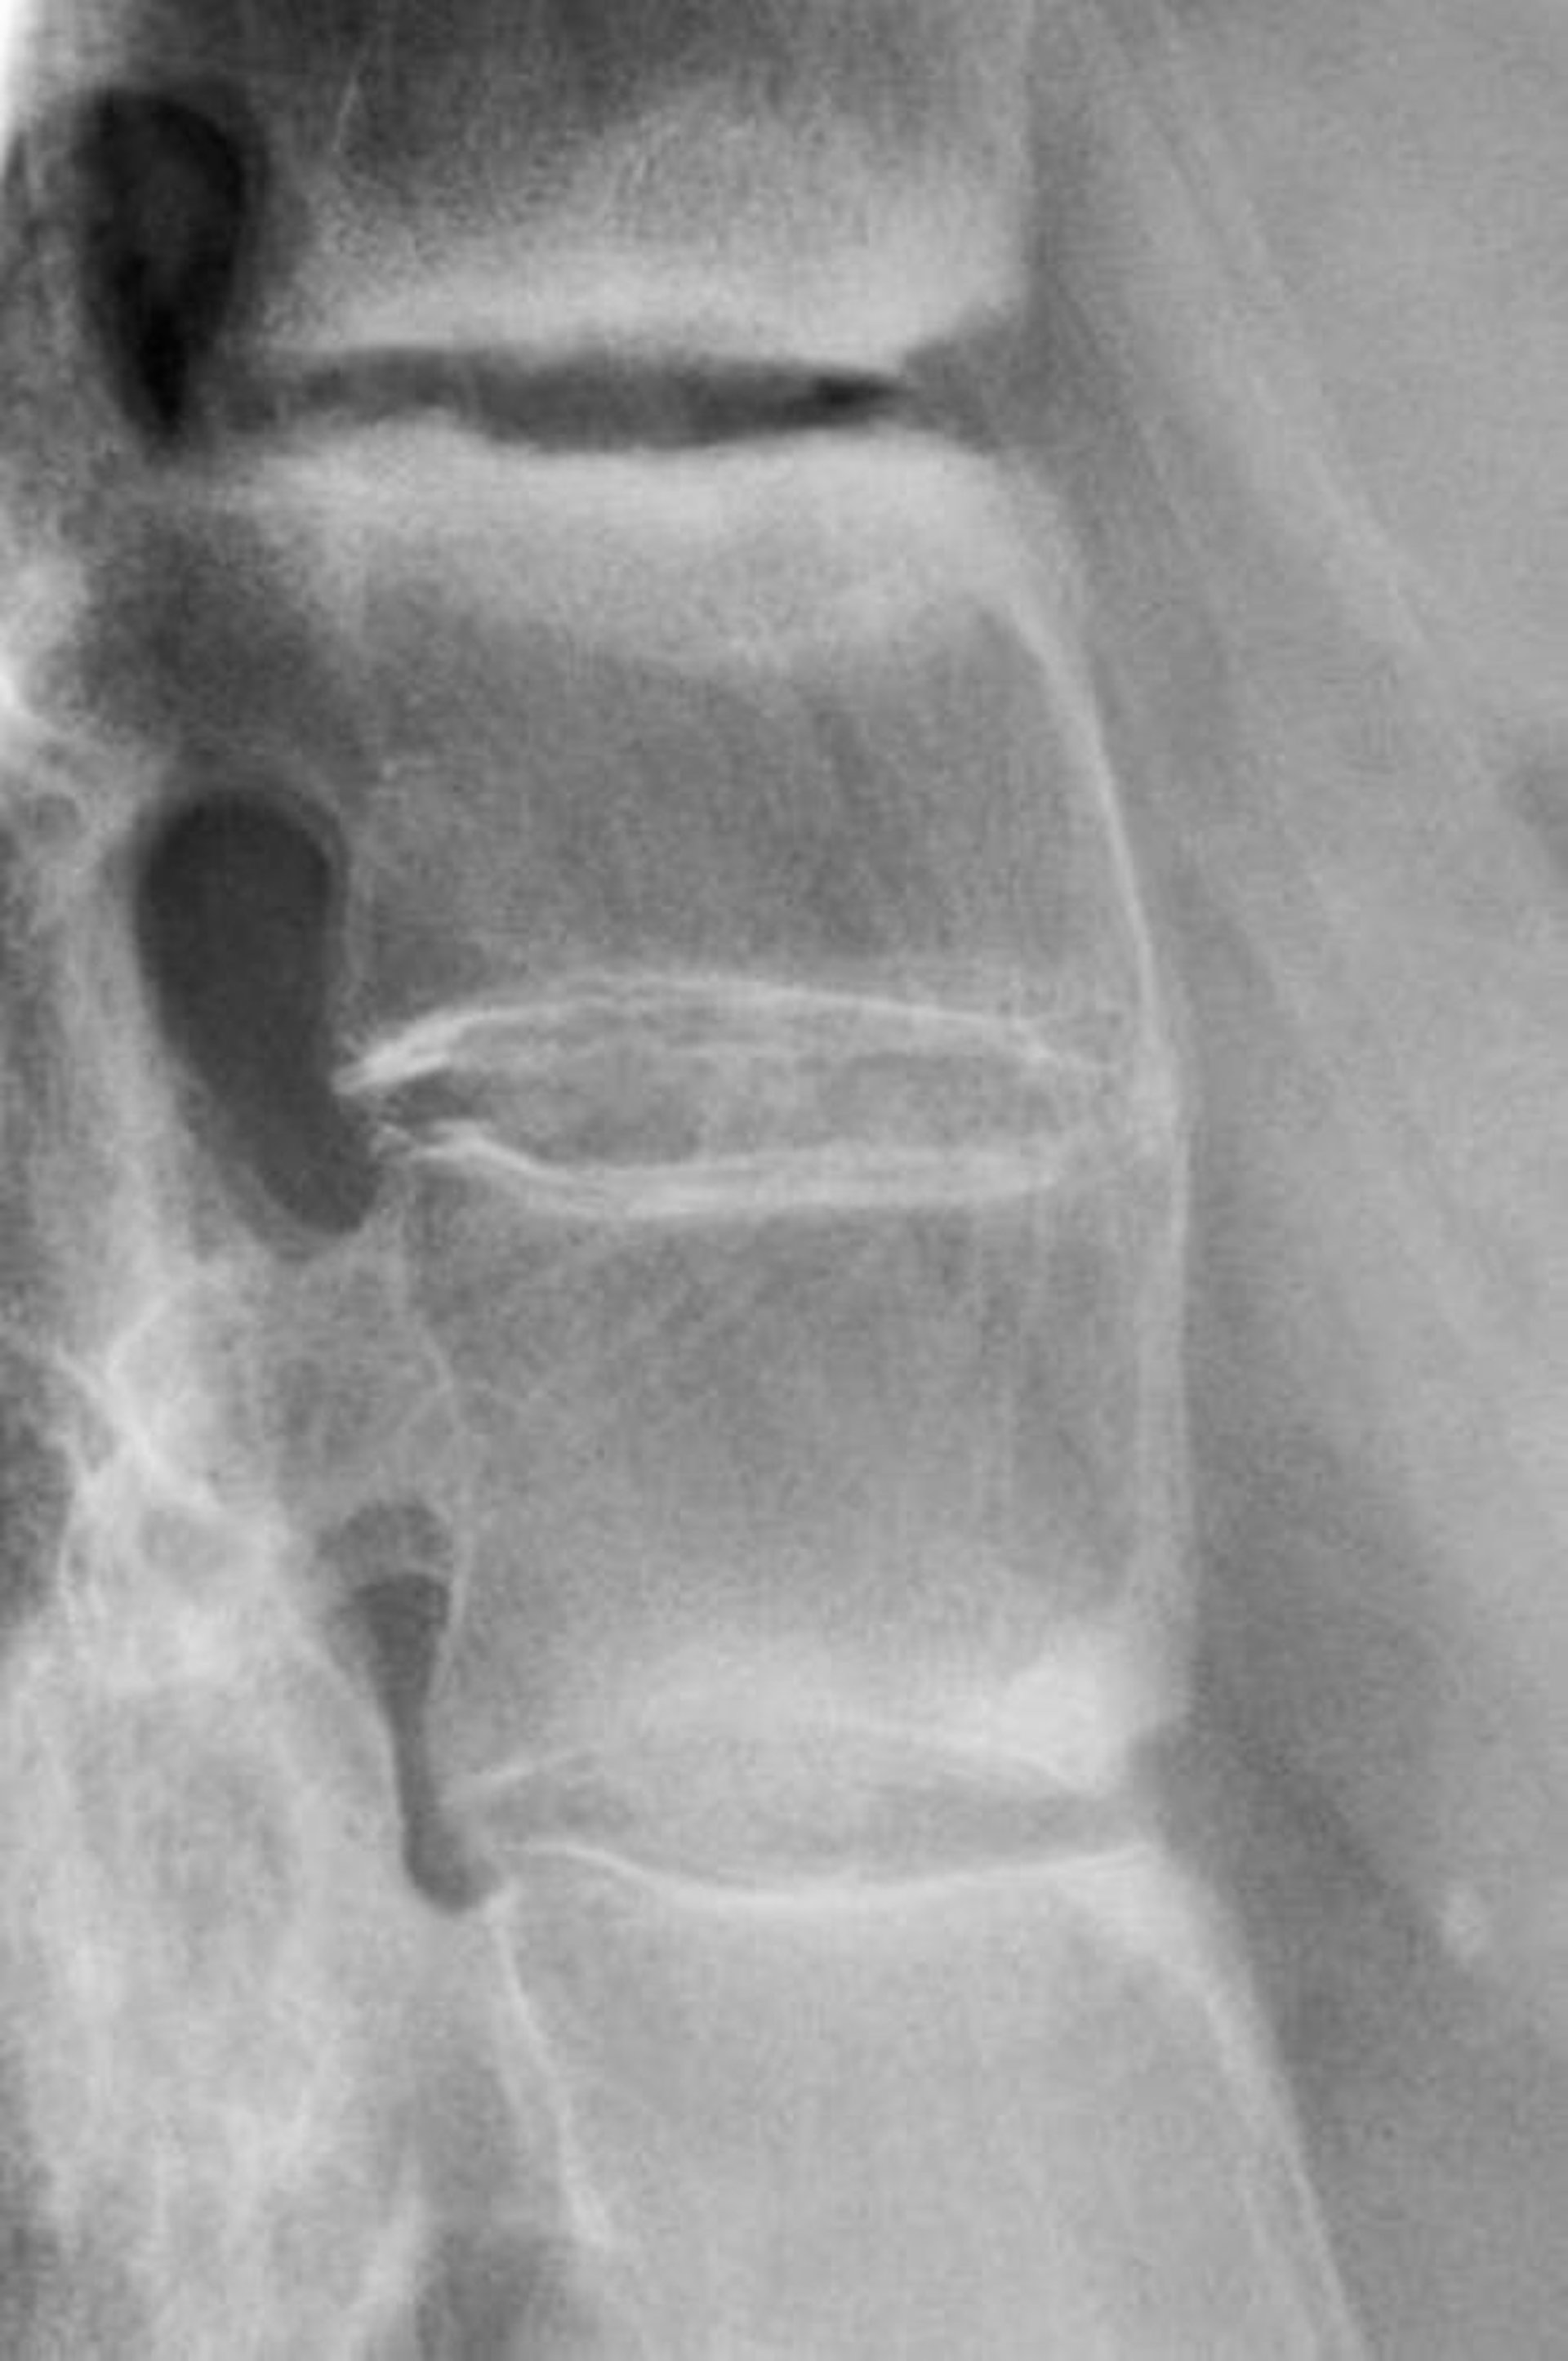

Spondylitis ankylosans

Diese Röntgenaufnahme zeigt eine Sklerose zwischen den Lendenwirbeln, einen Verlust der Lordose und eine Fusion der Lendenwirbel, ein Befund, der auf eine fortgeschrittene Spondylitis ankylosans hinweist.